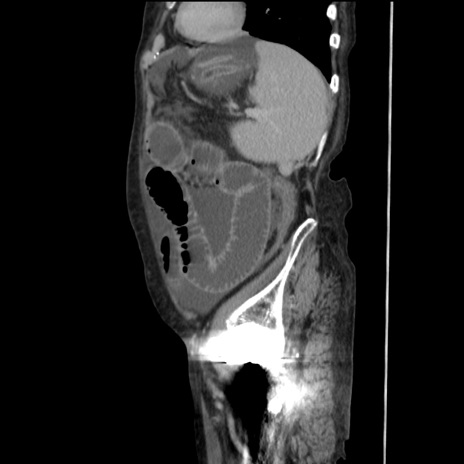

横断像

【症例】80歳代 女性

【主訴】腹部膨満感

【現病歴】他院にて肝硬変にてフォロー中。1週間前から便秘、腹部膨満感、臍部腫瘤あり受診となる。

【既往歴】肝硬変

【身体所見】腹部膨隆あり、皮膚変化なし、疼痛なし。

【データ】WBC 4600、CRP 0.25